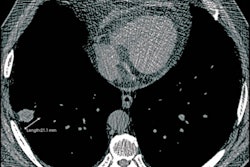

Out of the 5,057 with an incidentally detected lung nodule in the study, 38% were managed according to guidelines, 37% were managed less intensively, and 25% were more intensively managed.

Those who had more intensive management had an 8.1% higher rate of procedure-related adverse events compared with those managed according to guidelines. Furthermore, a post-hoc analysis showed that 72% of those who had a procedure-related adverse event did not have a lung cancer diagnosis within a two-year follow-up period.